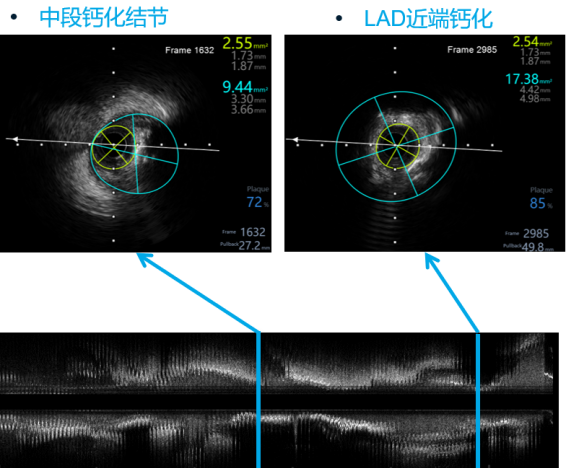

LAD IVUS-pre

沿LAD导丝送IVUS导管至LAD狭窄病变远段,检查示LAD-LM最小管腔直径1.58mm、最大管腔直径2.02mm、最小管腔面积2.4mm²,局部呈现270-360度钙化。

Shockwave 3.5*12mm于LAD-LM病变4atm-6atm反复震波扩张8次 每次10s

随后沿LAD导丝送入Shockwave 3.5*12mm球囊于LAD-LM病变处,由远及近,以4atm扩张触发血管内冲击波,每组10个,后将Shockwave导管扩张至6atm维持10-15s以检验扩张效果、最大化管腔获益,后回抱导管,进行下一组冲击波治疗,共循环发放8组脉冲,复查IVUS提示局部环形钙化环断裂。

严重钙化处管腔扩大